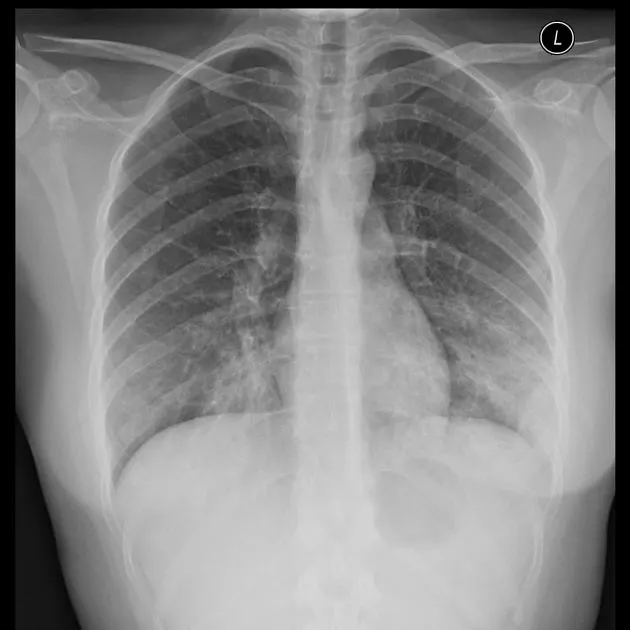

D1. Pneumococcal pneumonia

(1) Sudden onset of disease

: Rigors, Bloody sputum, High fever, and Chest pain with lobar infiltrates

(2) Responds to a variety of antibiotics, although there is penicillin-, macrolide-,and fluoroquinolone-resistant pneumococci

(3) Highly penicillin-resistant pneumococci require treatment with vancomycin, imipenem, a newer respiratory fluoroquinolone or ketolide